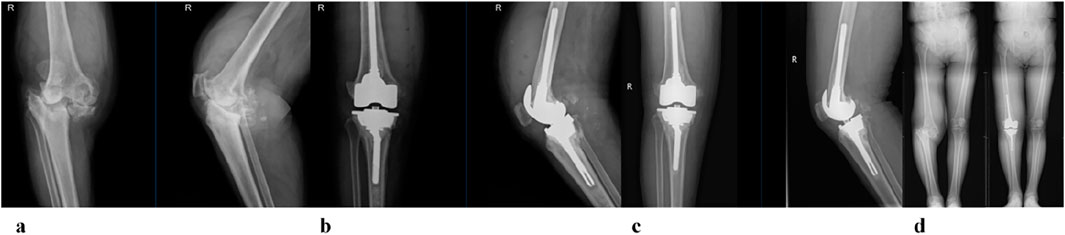

Clinical functional recovery was evaluated using the KSS scoring system, X-ray imaging to assess prosthesis position and bone integration, and gait analysis.The patient was followed up for 24 months. The preoperative KSS knee score was 46.5 ± 4.8. It was 80.1 ± 6.6 at 3 months postoperatively and 85.4 ± 5.5 at the last follow-up (Figure 12). At the last follow-up, there was no swelling, infection or postoperative complications at the surgical site. X-rays of the knee joint in anteroposterior position of all patients showed no adverse conditions such as radiolucency, loosening, or osteolysis around the 3D-printed ITP and bone surface (Figures 13A–C).

Figure 13

X-ray images labeled from a to d, showing a progression of knee evaluations. Image a displays a side view of an untreated knee joint. Image b shows a side view of the knee with joint replacements. Image c illustrates the knee with visible prosthetics in both front and side views. Image d presents a full lower body X-ray showing alignment and leg prosthetics.

Figure 13. A 65-year-old female patient with AORI Type III post-traumatic knee arthritis (PTKA) underwent 3D-printed integrated trabecular prosthesis (ITP) knee reconstruction. (a) Preoperative X-ray; (b) X-ray at 1 week post-surgery; (c) X-ray at the final follow-up; (d) Comparison of preoperative and postoperative lower extremity alignment.

Clinical evidence from 24-month follow-up of 6 patients further supports ITP’s value. The Knee Society Score (KSS) improved from 46.5 ± 4.8 preoperatively to 85.4 ± 5.5, exceeding the “good recovery” threshold (KSS >80). Radiologically, no periprosthetic radiolucency, loosening, or osteolysis was observed (Figure 12), aligning with Zerbo et al. (2003) findings that conforming prosthetic structures promote bone integration through enhanced osteocyte migration and vascular ingrowth (Zerbo et al., 2003). Gait analysis confirmed functional recovery: 1-year postoperative walking speed reached 1.08 m/s (meeting Studenski et al. (2011) “good functional status” standard) (Studenski et al., 2011), step length increased by 15.8% (45.4 cm–52.6 cm), and stance/swing-phase symmetry approached that of the contralateral limb—outcomes rarely achieved with MAP due to imprecise defect filling.